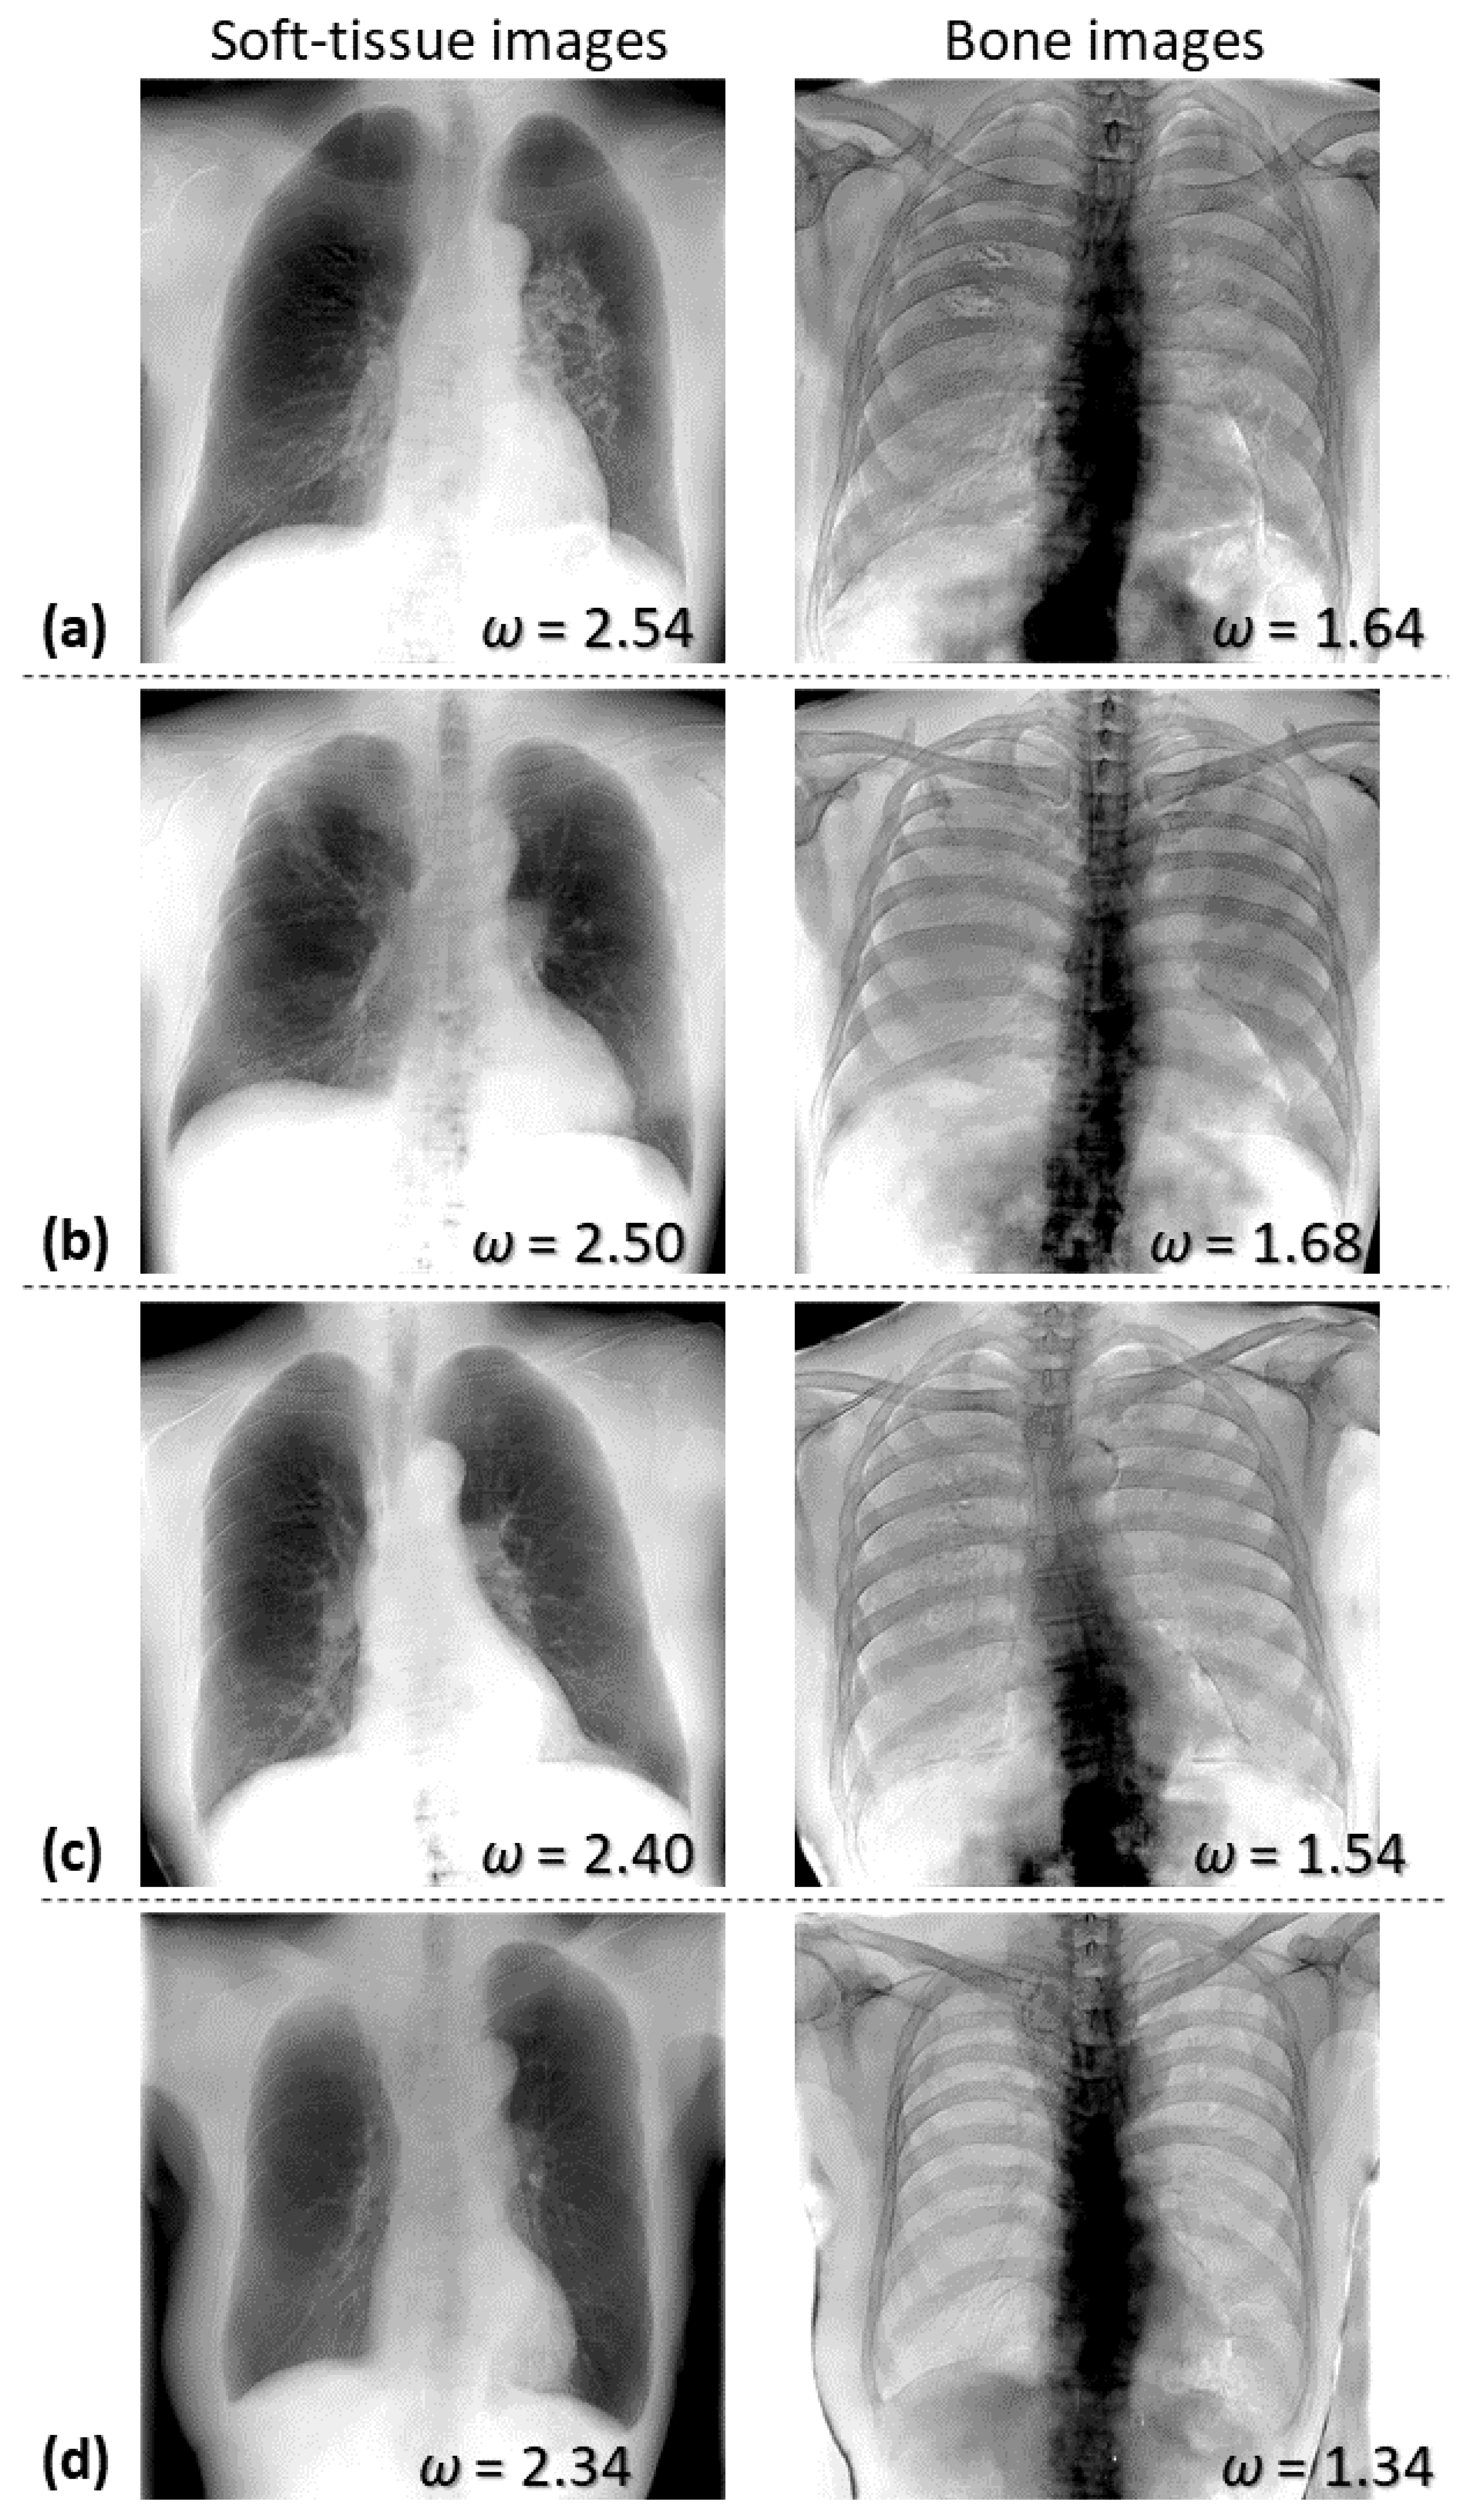

Figure 5 shows soft-tissue- and bone-enhanced images generated using Equation (10) for four test cases. The weight factors () used in the weighted subtraction are presented in the lower-right corner of each image. As shown in the left column in Figure 5, the soft-tissue-enhanced images demonstrate that the soft tissues were well-retained, and bone tissues were effectively suppressed, although the edges of the clavicles, ribs, and spine are faintly presented. On the other hand, as seen in the right column in Figure 5, the bone-enhanced images exhibited relatively suppressed soft tissues. However, the enhanced lower thoracic and lumbar spine are poorly visualized, as they appear to be blacked-out.

Figure 5.

Examples of soft-tissue- and bone-enhanced images generated by AI-DES for four test cases (a–d). The weight factors used in the subtraction process are presented in the lower-right corner of each image.

Table 3 presents the average and standard deviation of PSNR, SSIM, and MS-SSIM values across all test cases, evaluating the similarity between soft-tissue-enhanced images obtained using AI-DES and Discovery XR656, as well as the similarity between bone-enhanced images. Additionally, Table 3 includes weight factors used in weighted image subtraction of AI-DES, as well as the similarity indices between the real and virtual 60 kV images, as explained in Section 3.1. The PSNR, SSIM, and MS-SSIM values for soft-tissue- and bone-enhanced images are significantly lower than the indices for 60 kV images. Table 3 also demonstrates that the values of varied slightly among patients, but values for soft tissue enhancements were consistently higher than those for bone enhancements.